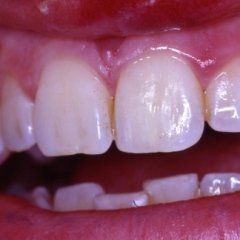

L’enorme diffusione ancora oggi riscontrabile della carie dentaria, unita a traumi, difetti di mineralizzazione o ipoplasie dello smalto determinano la necessità di dover ricorrere ad un restauro dei tessuti dentari lesionati. Il continuo miglioramento dei materiali e di conseguenza delle tecniche hanno altresì ampliato il raggio di azione della cosiddetta conservativa che con il ricorso al trattamento endodontico in caso di lesioni particolarmente gravi, occupa circa i due terzi dell’attività del dentista. In considerazione di questo fatto quindi, oltre all’evidenza che il trattamento restaurativo diretto è in genere il primo atto odontoiatrico che si effettua su una corona dentale lesionata, emerge la necessità che questa terapia sia ben eseguita ed in armonico rapporto con le strutture parodontali ed endodontiche.